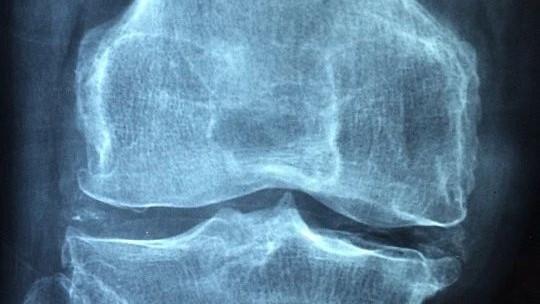

骨质疏松症是中老年人群必须要面对的重要健康问题,有统计显示,50岁以上男性骨质疏松症患病率为6.0%,女性患病率则达到32.1%,65岁以上女性的骨质疏松症患病率更是达到51.6%。此外,还有大量人群骨量非常低,成为骨质疏松症的“后备大军”。

骨质疏松其实是一种全身性疾病,根据病因的不同可以分为三类,第一大类是与绝经、年龄大有关的,称为原发性骨质疏松,多见于中老年人。第二大类是与疾病或药物有关,称为继发性骨质疏松,常见的一些疾病如甲亢、1型糖尿病、肝胆疾病、类风湿、痛风、慢性肾病等,以及一些药物如糖皮质激素、肝素、甲氨蝶呤等,均会导致骨质疏松,这一类可见于任何年龄段。最后还有一类是特发性骨质疏松,与骨代谢调节异常有关,比如青春期生长,或者妊娠期及哺乳期,“需求”突增,骨形成和吸收的平衡被打破,也会导致骨质疏松。